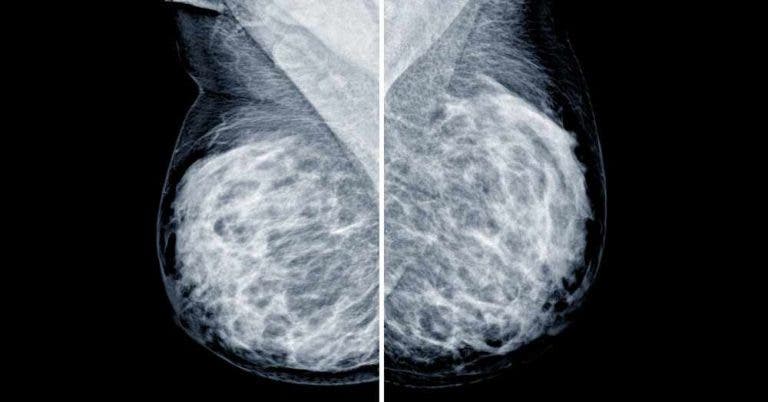

- Faire une mammographie tous les deux ans pour les femmes âgées entre 50 et 74 ans.